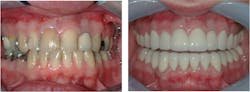

However, when blended with the clinical experiences of long-term CR clinicians, this information should be useful for you and your patients. The example in Figures 1 and 2 shows a patient who was not told by the practitioner that his previous restorations would eventually need to be replaced. This is the situation with many patients.